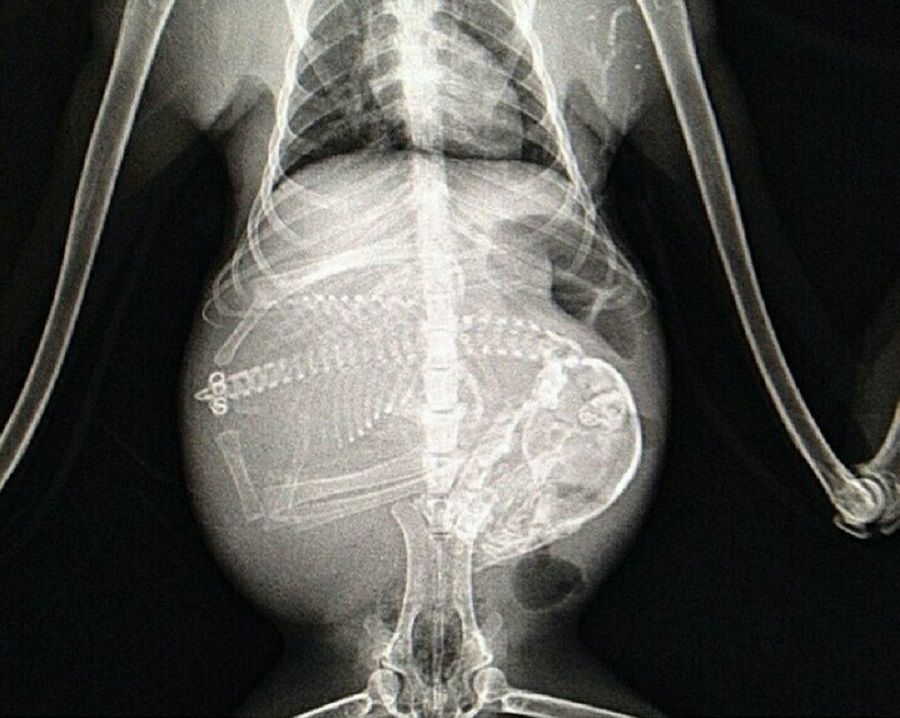

Mrówniki afrykańskie, nazywane też prosiętami ziemnymi, to łożyskowce z rodziny mrównikowatych, żyjące wyłącznie w Afryce. Prowadzą samotny, nocny tryb życia, a pokarm znajdują, grzebiąc w ziemi. Jak widać na zdjęciach, pomagają im w tym imponujące pazury.